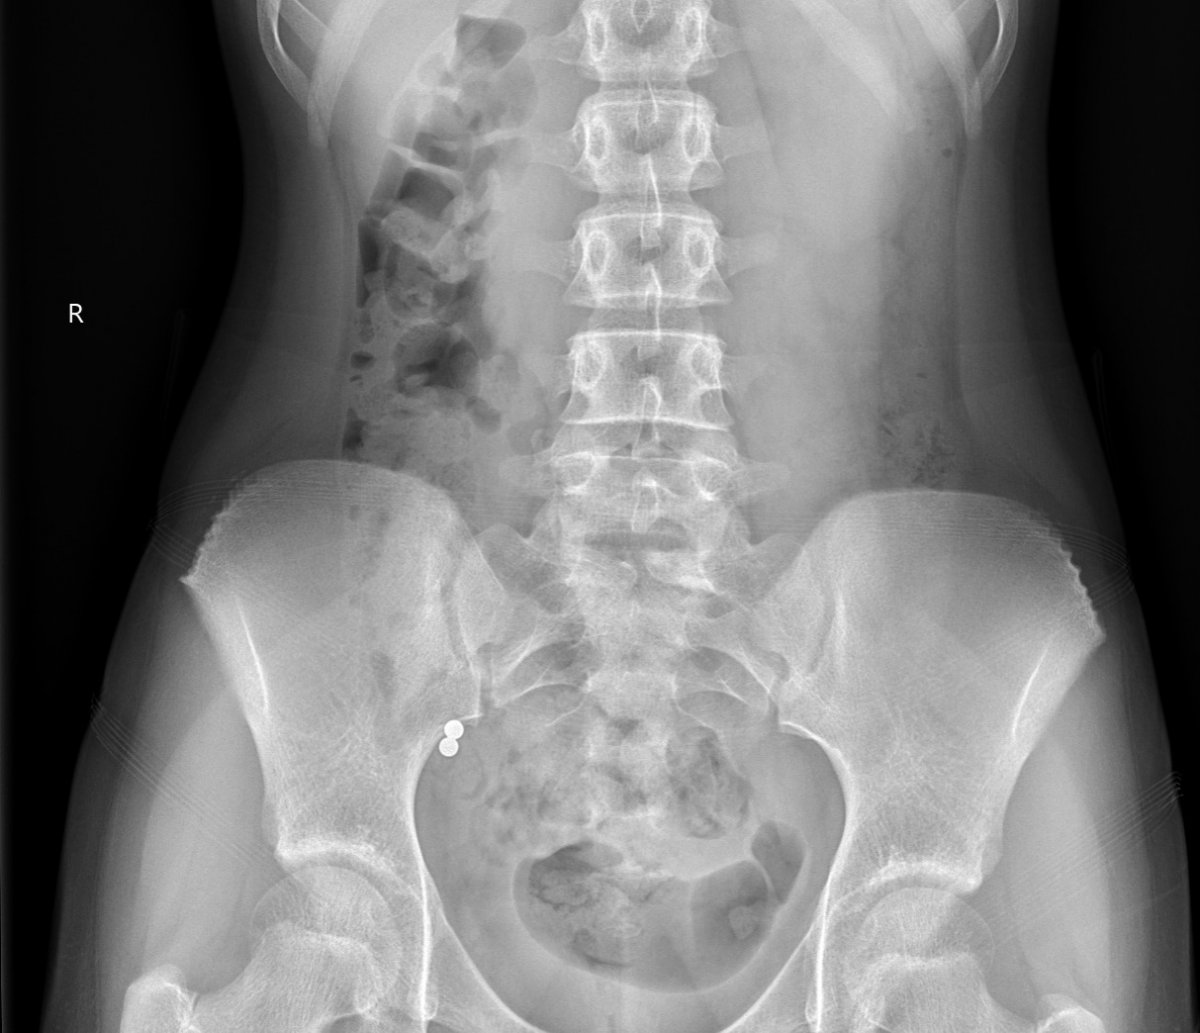

Galéria k článku Rodičia, POZOR! Šíri sa NEBEZPEČNÝ TikTok trend: Viacero detí skončilo v nemocnici

Zdroj: FN Motol